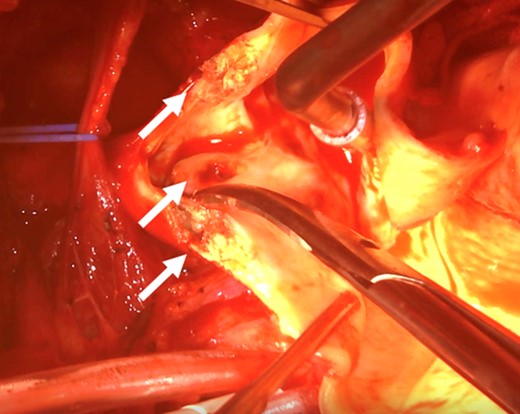

After admission, carotid ultrasonography revealed a large, soft plaque with ulceration in the IA and a very mobile soft plaque in the LSA (Fig. 3). EVT was thus considered too dangerous, and TAR using a four-branched prosthesis was planned. Intraoperatively, bilateral axillary arteries were initially exposed, and an 8-mm vessel prosthesis was anastomosed. Median sternotomy was then performed. Cardiopulmonary bypass was established with arterial perfusion via bilateral axillary arteries and bicaval venous drainage. TAR was performed under hypothermic circulatory arrest with antegrade selective cerebral perfusion, then the brachiocephalic artery and LSA were clamped and the left common carotid artery (LCA) was intubated. To avoid hoarseness due to injury of the left recurrent laryngeal nerve, a hybrid prosthesis (FROZENIX, Japan Lifeline, Tokyo, Japan) was used and a distal anastomosis was created between the LCA and LSA. The LCA was ligated and the prosthesis, which was anastomosed to the left axillary artery, was brought into the mediastinum and anastomosed with a branch of the four-branched prosthesis (Fig. 4). The postoperative course was uneventful and the patient was discharged on postoperative day 16 (Fig. 5).